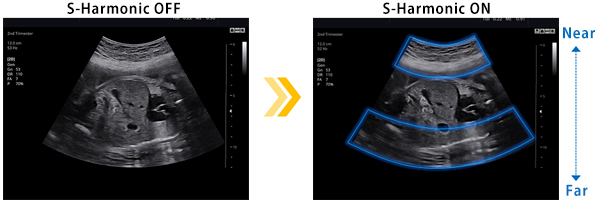

S-HARMONIC

Gürültüyü azaltır ve yakın mesafeden görüntünün netliğini ve homojenliğini sağlar. Daha fazla görüntü kalitesi gelişimi için ClearVision ve MultiVision ile birlikte kullanın.